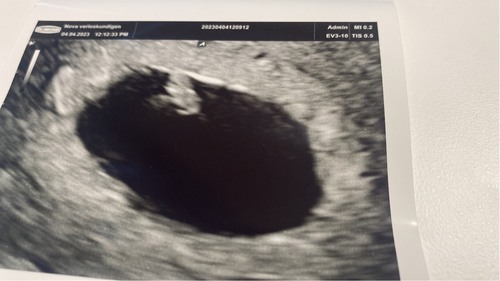

Hoera! We hebben een goede echo met een hartslag ❤️